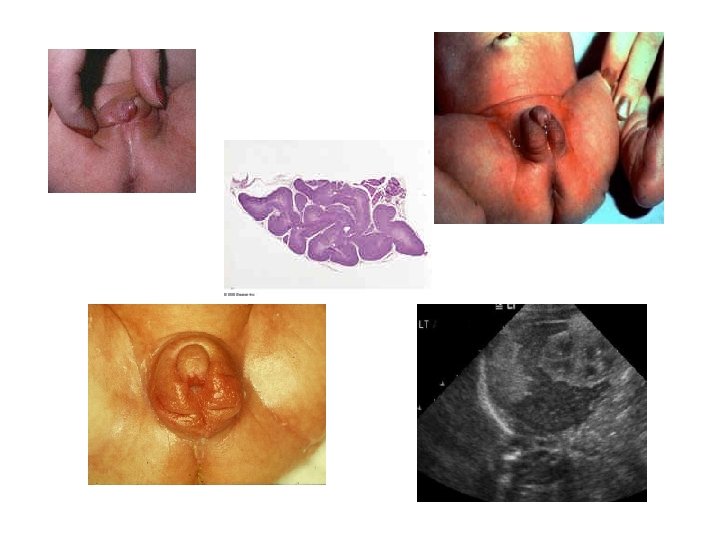

Associated conditions The symptoms of CAH vary depending upon the form of CAH and the gender of the patient. Symptoms can include: • Due to inadequate mineralocorticoids: - vomiting due to salt-vasting leading to dehydration and death • Due to excess mineralocorticoids: - hypertension (11 β-OH deficiency) • Due to excess androgens: - ambiguous genitalia in some females, such that it can be initially difficult to determine sex - early pubic hair and rapid growth in childhood - precocious puberty or absent or delayed puberty - virilization (enlarged clitoris and shallow vagina), and/or menstrual irregularity in adolescence - infertility due to anovulation

Symptoms 1. • Infants born with CH may show no effects, or may display mild effects that often go unrecognized as a problem (!) • If fetal deficiency was severe because of complete absence of the gland, physical features may include more characteristic signs

Classic signs: excessive sleeping, reduced interest in nursing, bad appetite, poor muscle tone, low or hoarse cry, infrequent bowel movements, constipation, exaggerated jaundice, low bodytemperature, dry skin, larger anterior fontanel, persistence of a posterior fontanel, umbilical hernia, large tongue (macroglossia), lethargia, wide nasal sella, oedema, bradycardia and sometimes - goiter.

Symptoms 2. • In the era before newborn screening, less than half of cases of severe hypothyroidism were recognized in the first month of life (!) These infants would grow poorly and be delayed in their development. • By several years of age, they would display the recognizable facial and body features of cretinism with severe mental and physical retardation, with an IQ below 80 in the majority.